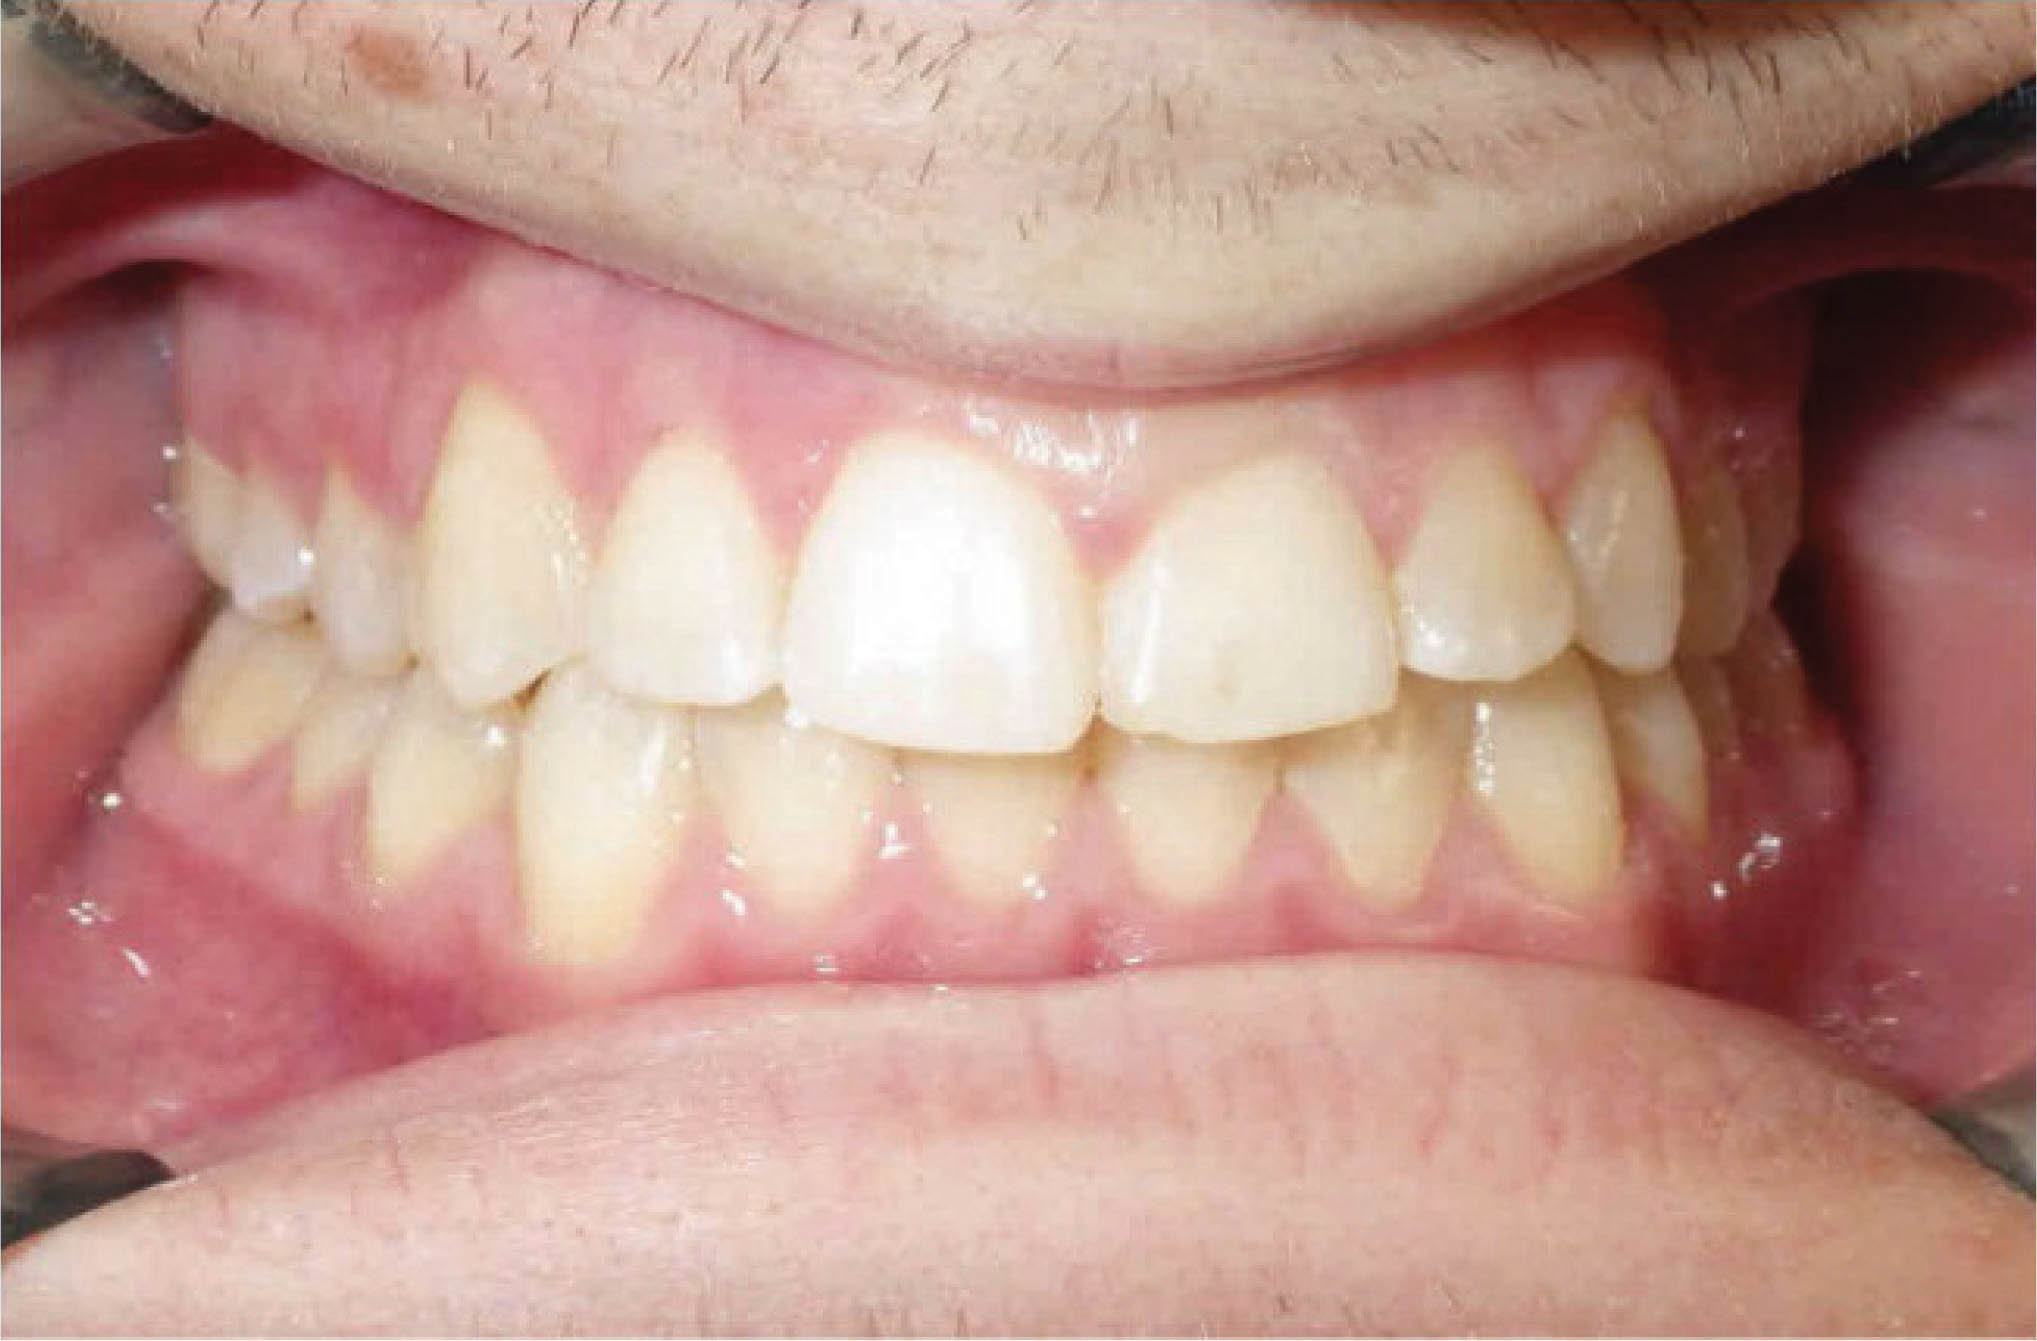

سومین کاربرد استریپ اصلاح اورجت در بیماران کلاسII یا III است. اکلوژن بیمار شکل 147-6 کلاسIII است. در این بیمار از پایین استریپ کردیم تا با حرکت خلفی قدامیها به اورجت مطلوب و رابطه کانینی کلاسI برسیم. البته در این بیمار از الاستیک کلاسIII هم استفاده گردیده است. استریپ خلفی در هر دو سمت انجام گردید.

نتایج درمان در شکل 149-6 مشخص است.

شکل 147-6

شکل 148-6

شکل 149-6